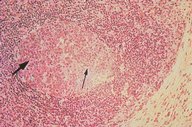

Normal reactive follicle

This is a very low power H&E view of a normal,

non-malignant, reactive lymph node. Follicular

hyperplasia is seen, both in the central and

cortical areas.